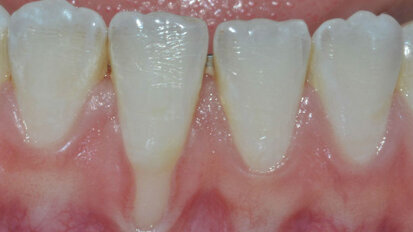

Terapia parodontale non chirurgica con approccio “One-Stage Full-Mouth Disinfection”

Le malattie parodontali possono causare gravi invalidità quali la perdita o la riduzione della funzionalità dell’apparato ...